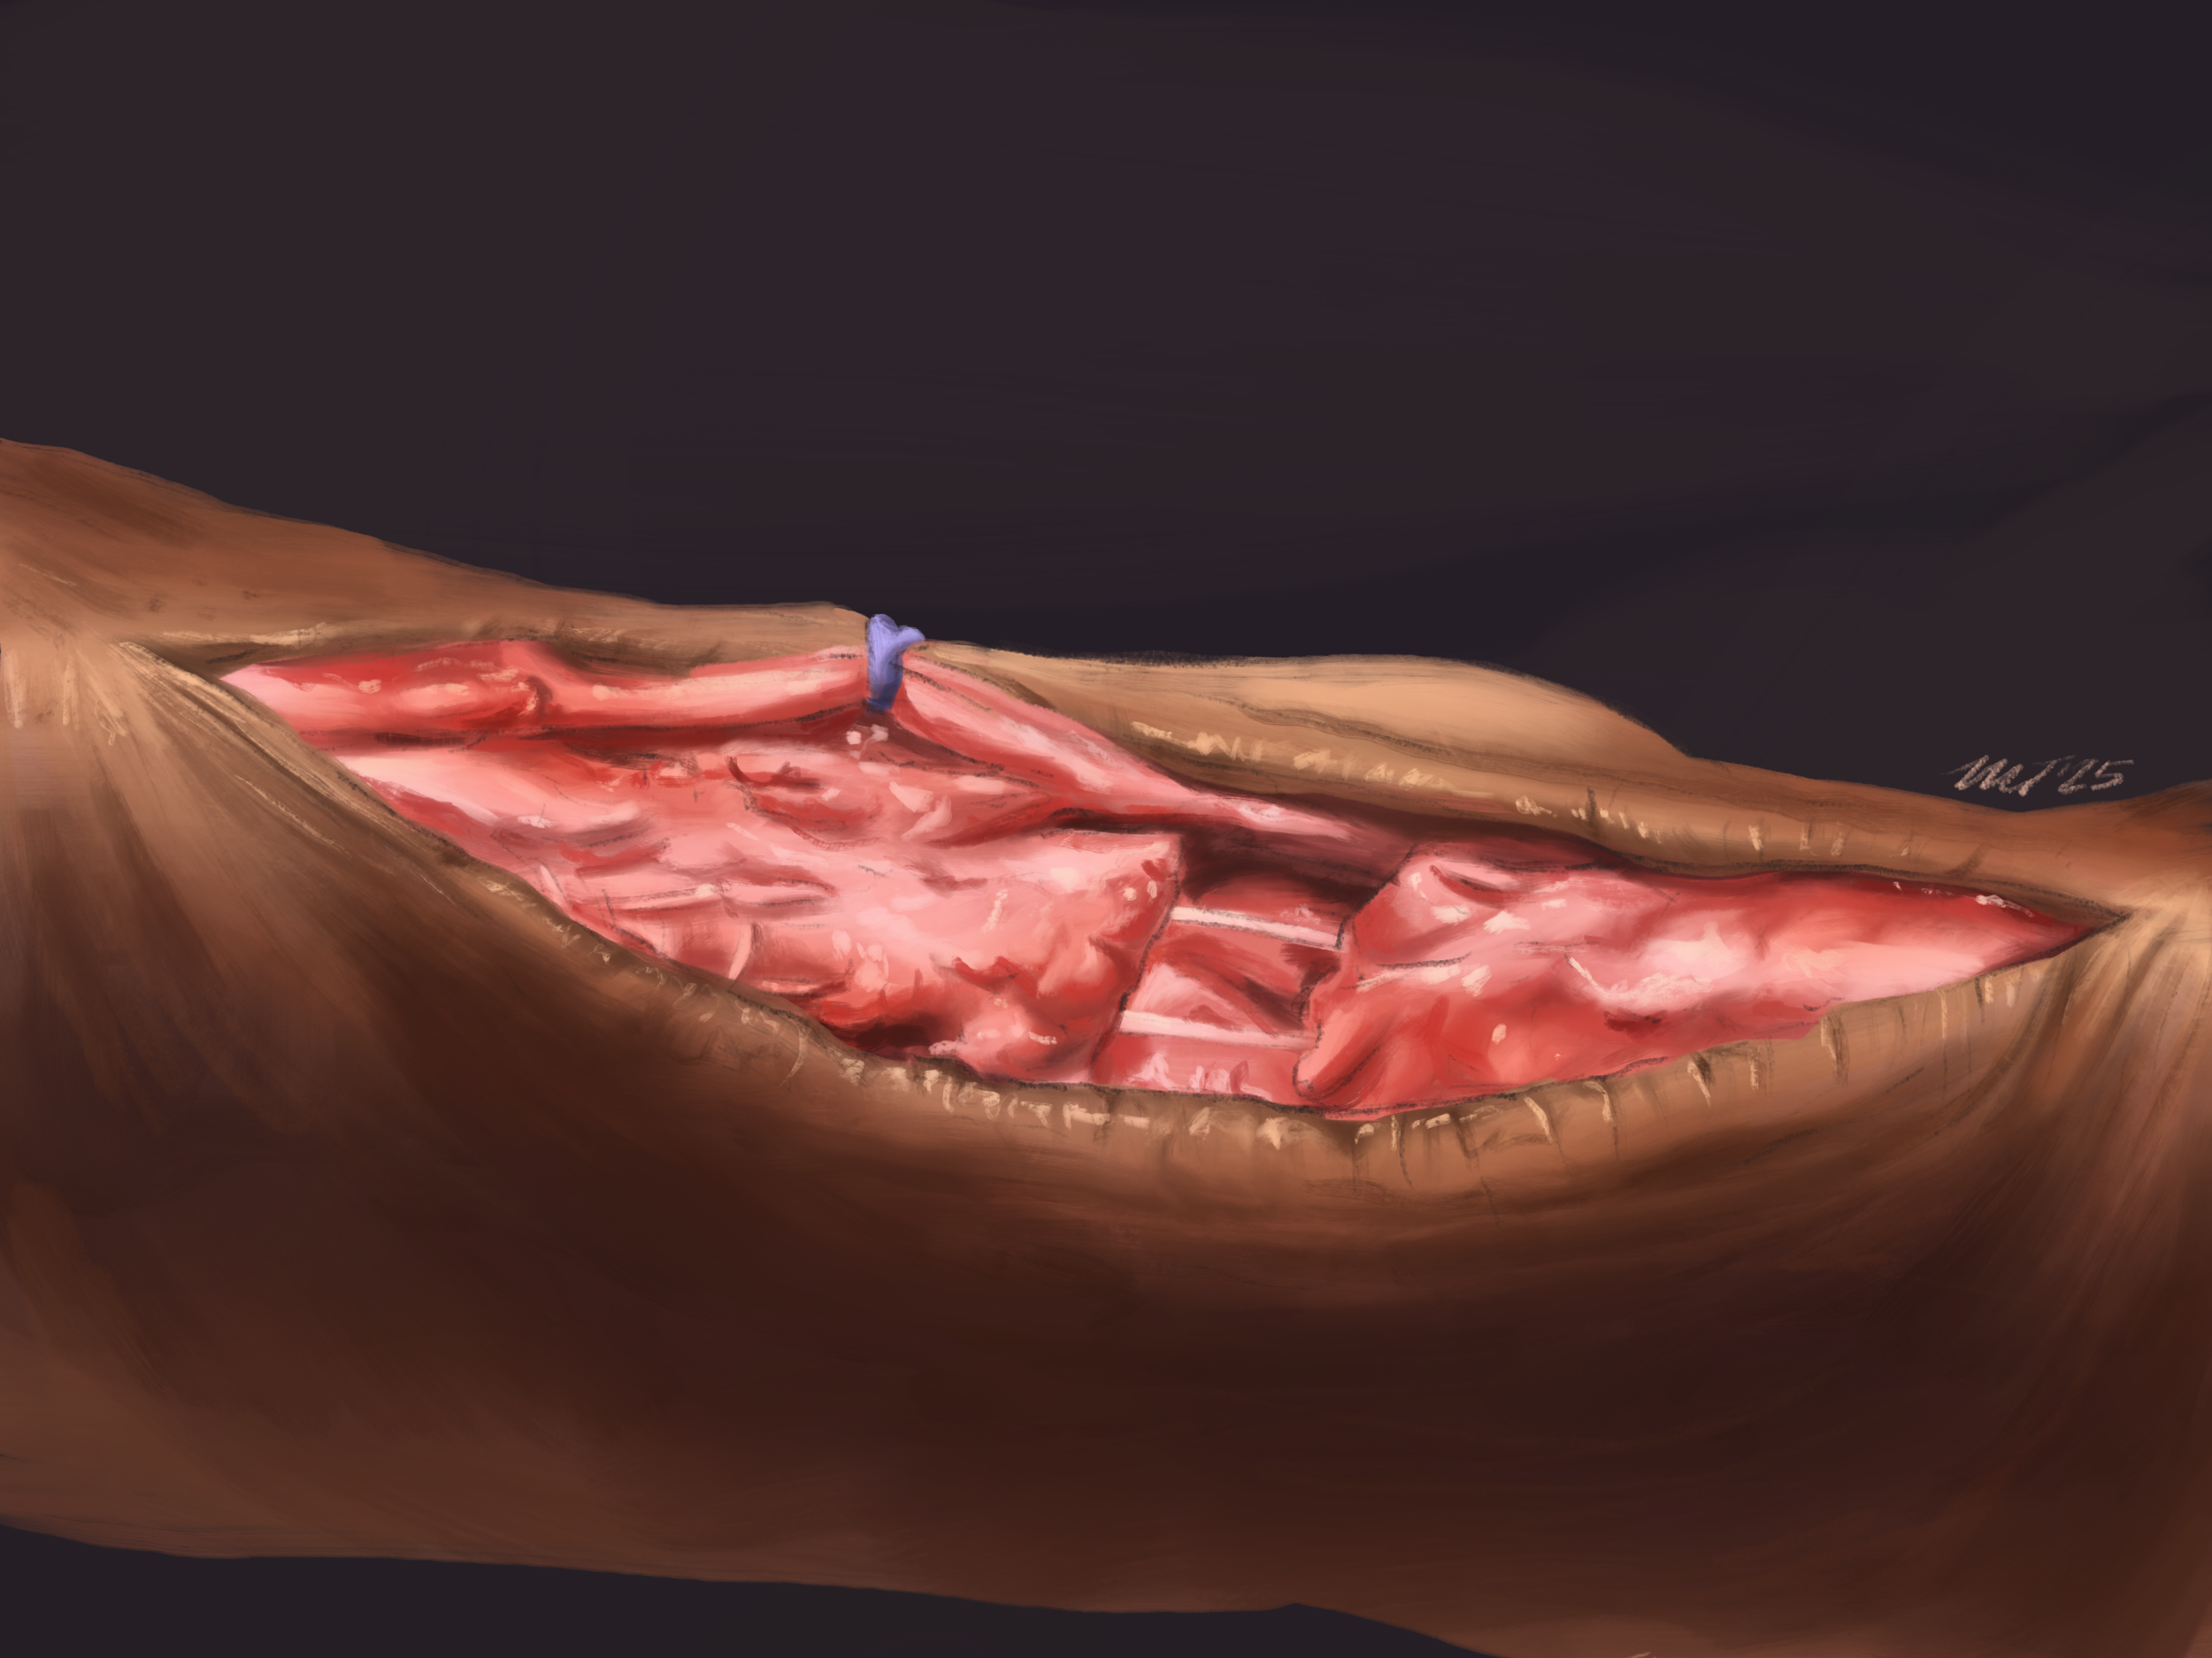

Tissue reaction study: Achilles tendon repair